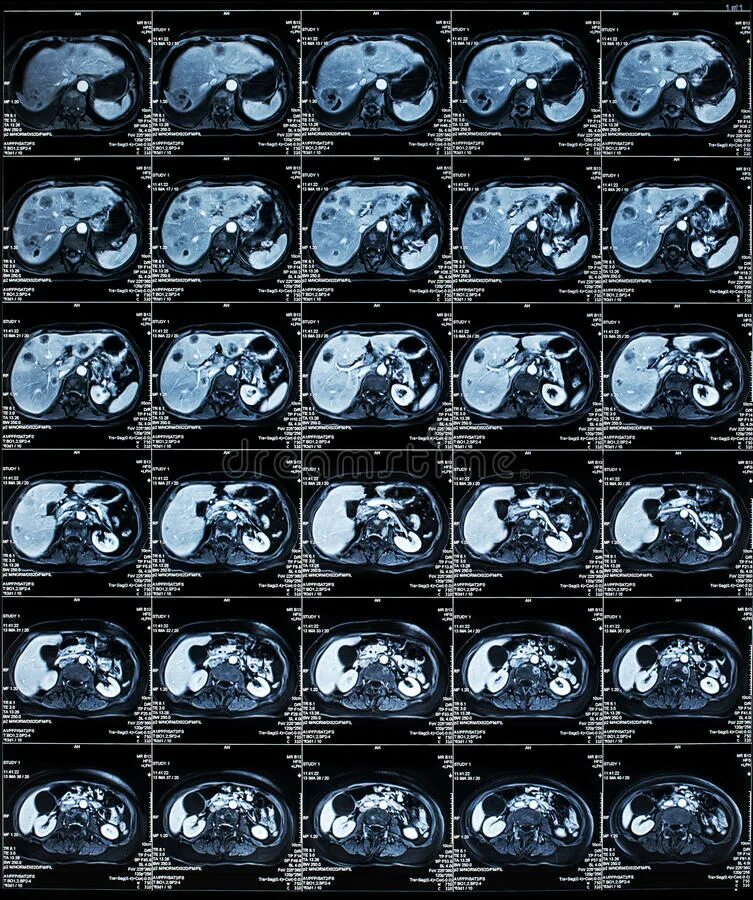

Подготовка к кт грудной и брюшной полости